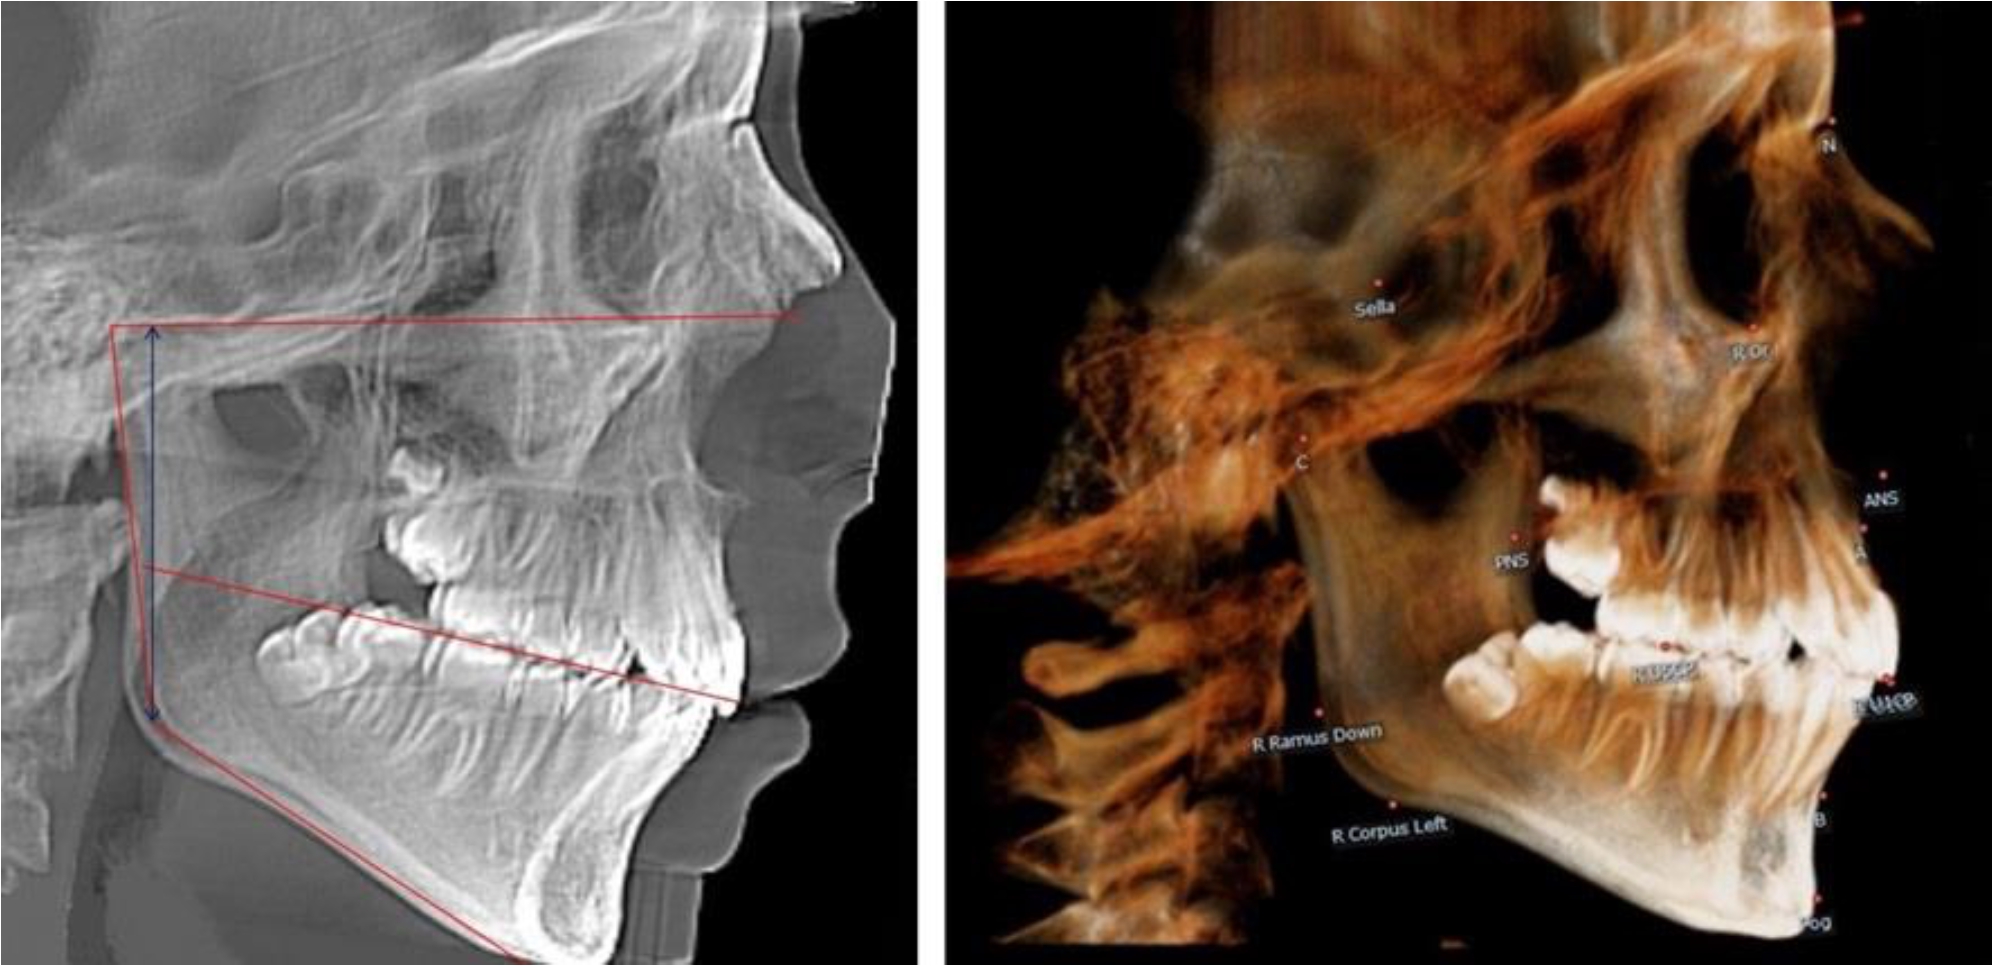

В 4-й группе были проанализированы 12 комплектов рентгенограмм, что составило (11,32 ± 3,08) % от общего числа. На всех рентгенограммах произошла полная смена всех молочных зубов постоянными. Окклюзионная линия делила ветвь на два отдела (рис. 4).

Рис. 4. ТРГ пациента после смены всех молочных резцов

Высота ветви у детей 4-й группы составляла (54,27 ± 2,59) мм, что было достоверно больше, чем у детей 1-й группы (р ˂ 0,05). При этом высота верхней окклюзионно-суставной части была (32,51 ± 1,72) мм, а нижней – (21,76 ± 1,42) мм. Высота верхней части была больше нижней, что и определяло особенности соразмерности частей ветви нижней челюсти в анализируемый возрастной период.

Относительные показатели соразмерности частей ветви нижней челюсти показали, что отношение высоты верхней части ветви к нижней в среднем составляло 1,49 ± 0,12. Отношение общей высоты ветви к верхней ее части составляло 1,67 ± 0,14, а отношение общей высоты ветви к нижней ее части было 2,49 ± 0,15, что и определяло особенности соразмерности частей ветви нижней челюсти в анализируемый возрастной период.